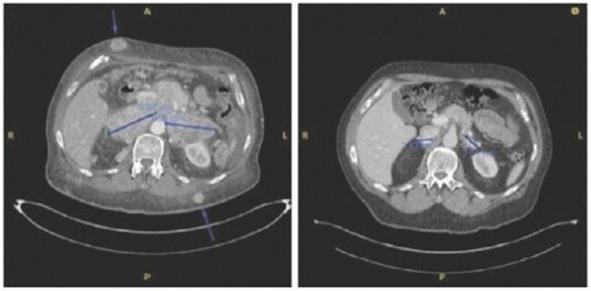

Patients Merkel cell carcinoma-03 and Merkel cell carcinoma-05 below demonstrate the abscopal effect of adjunctive IFx-2.0 therapy, These patients exhibited primary resistance to checkpoint inhibitor therapy, and subsequently achieved durable anti-tumor responses following IFx-2.0 and rechallenge with checkpoint inhibitor therapy.

Case study (MCC-005)

Patient was treated for multifocal in-transit recurrence of Merkel cell carcinoma in left leg with avelumab x 6 doses (12 weeks) with continued rapid clinical progression as well as development of liver metastatic disease on this therapy. Subsequently the patient was enrolled on IFx-2.0 protocol and received 3 weekly injections of IFx-2.0 without complication but continued clinical progression (additional in-transit sites). Disease status at time of last injection shown on the left. Following completion of IFx-2.0 protocol therapy, subject was rechallenged with pembrolizumab, a checkpoint inhibitor, and experienced an obvious clinical response initially apparent approximately 3-4 weeks into therapy. Clinical response at 3 months (middle photo below) and 6 months (right photo below) are shown in the photos below. Concordant (near-complete) radiographic response of liver metastases has also been observed and response has been maintained to date (19 months)

Case study (MCC-002)

Subject was treated with adjuvant pembrolizumab for stage II Merkel cell carcinoma on the STAMP trial but developed (nodal) progression after receiving 6 doses. Subject underwent salvage surgery/XRT but developed widespread metastatic disease ~3 months later (nodal, dermal, and intramuscular sites of disease). Subject was then enrolled on IFx-2.0 protocol and received 2 weekly injections to 3 nodal/dermal metastatic sites but experienced continued rapid progression (both injected and non-injected sites) including bulky diffuse adenopathy and numerous widespread subcutaneous/dermal nodules. Representative imaging from the time of completion of protocol therapy is shown on left in photo below including several subcutaneous sites (as noted by the arrows) and bulky retroperitoneal (“RP”) conglomerate lymph node (“LN”) metastases. Post-protocol, subject was started on checkpoint inhibitor rechallenge with avelumab and experienced deep partial response that has been maintained to date (33 months). Representative images from post-checkpoint rechallenge restaging shown below on right (complete remission of subcutaneous nodules, partial response in retroperitoneal sites).